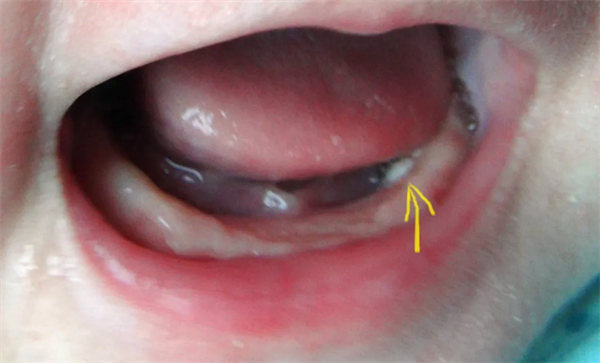

10. 口腔里的“小白點”?是“馬牙”,別挑破!

在寶寶口腔上顎中線或牙齦上,可能看到黃白色、米粒大小的小顆粒,這是“馬牙”,是上皮細胞堆積或黏液腺分泌物潴留形成的,數周后會自然脫落。

重要提醒:絕對不能用牙簽、針去挑破,以免引起口腔感染,甚至導致敗血癥。